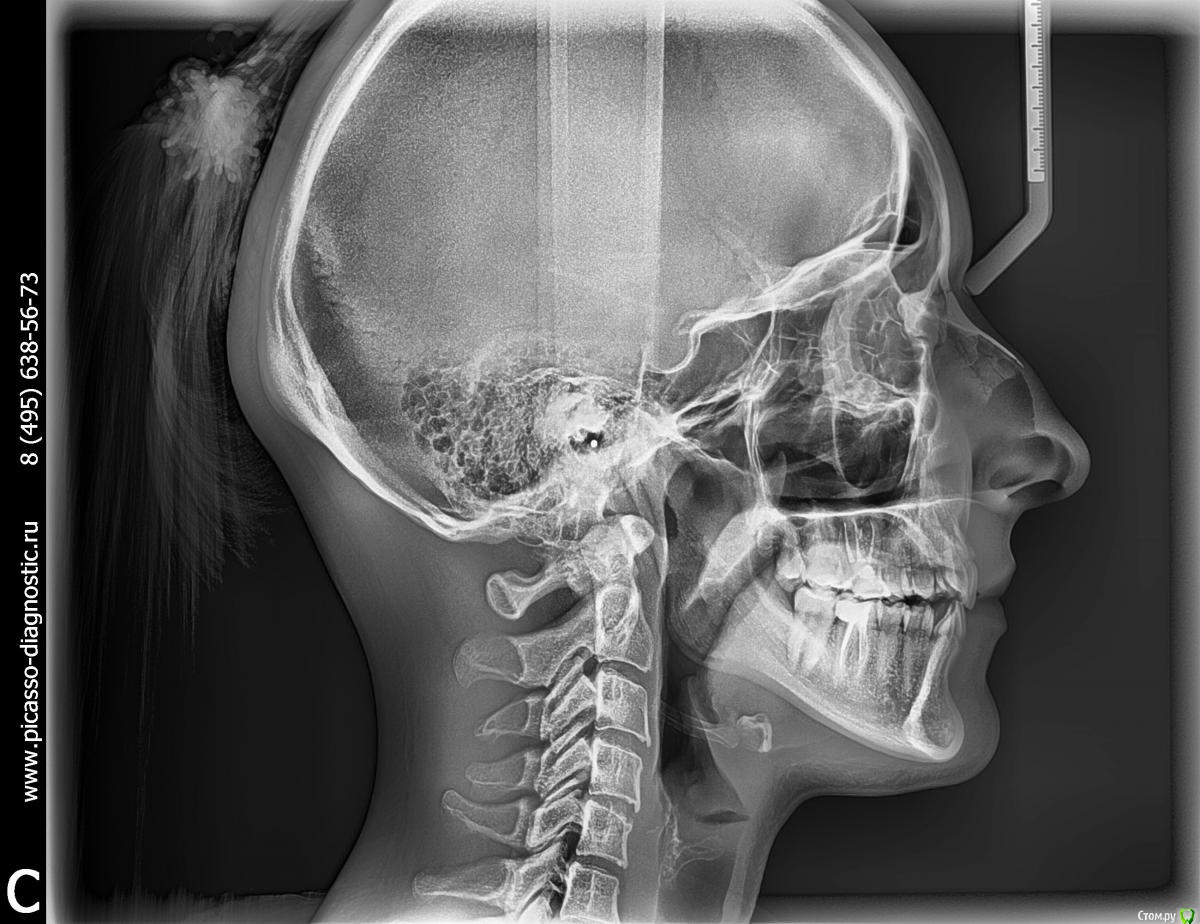

Jason Fa Опубликовано 1 мая, 2015 Поделиться Опубликовано 1 мая, 2015 Здравствуйте! Мне 23 года. Я планирую ортодонтическое лечение. С рождения у меня адентия резца 2.2. Клык встал на его место. Был недоразвит и его нарастили под резец около 7 лет назад. На правой стороне был ретенированный клык 1.3, который я приняла решение удалить и удалила (о чем сейчас жалею. Операция прошла крайне неудачно). То есть сейчас эстетически у меня нет обоих клыков на верхней челюсти. И щели между зубами. Рассматриваю два варианта:1. Открытие промежутков и импланты2. Закрыть промежуткиБыла на консультации у 3 ортодонтов. Все три предложили закрывать промежутки. Хотела бы уточнить как лучше быть. Прилагаю ТРГ и панорамный снимок. Панорамный снимок сделала в марте. До удаления клыка. ТРГ сделано позавчера. Сейчас нахожусь в стадии лечения 6рок и мелких кариесов. Знаю, что на закрытие должны быть определенные показания: гнатическое соотношение, профиль, контакты зубов. Хотелось бы понимать как изменится челюсть, профиль, форма губ, подбородка при таком закрытие. Буду благодарна за ответы! Заранее спасибо! Ссылка на комментарий

Jason Fa Опубликовано 6 мая, 2015 Автор Поделиться Опубликовано 6 мая, 2015 Вот как лежал клык Ссылка на комментарий